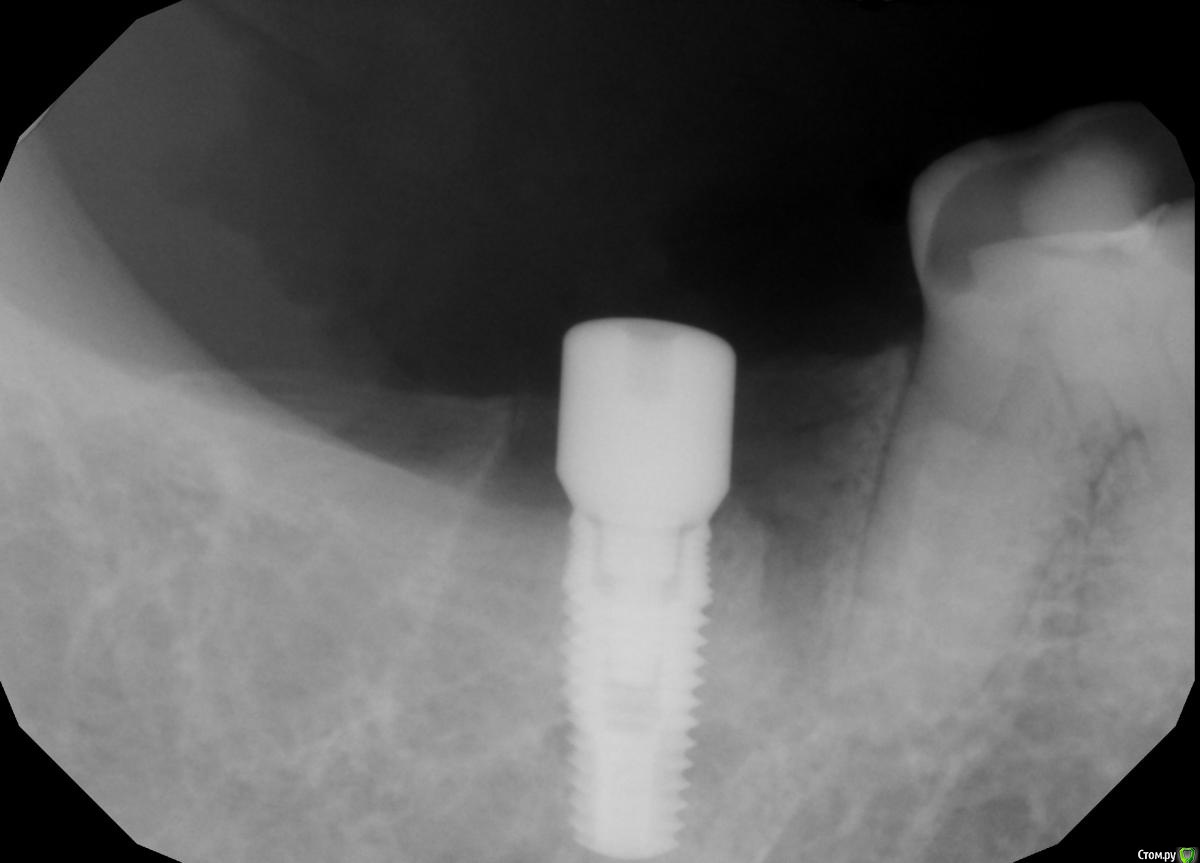

Demerchyan26 Опубликовано 3 марта, 2016 Поделиться Опубликовано 3 марта, 2016 Решил показать свой небольшой эксперемент. Ничего необычного, сложное удаление 1 час + имплантация, только без графта, лишь сгусток и торк меньше 5, не мог заглушку прикрутить. Открывал через 3,5 - 4 месяца. Система бюджетная - SGS, 7-ку немного не докрутил))) Ссылка на комментарий

Demerchyan26 Опубликовано 3 марта, 2016 Автор Поделиться Опубликовано 3 марта, 2016 С десной будем работать, есть дефицит, в этот день видимо не с той ноги встал)))Только что снимок, у другой пациентки, тоже без графта, срок 2 месяца, сегодня ставили в другом сегменте, решил сделать снимок. Ссылка на комментарий